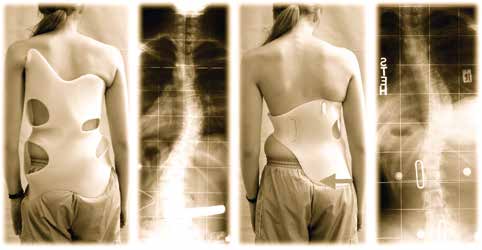

Vorläufer der heute vom Autor angewendeten CAD-/CAM-Versorgungen waren eigene Modifikationen, nachdem das von Chêneau empfohlene Modell 2000 nicht die gewohnten Korrekturen ermöglichte. Es war immer ein Anliegen des Autors, die Korsette für die Patienten kleiner und angenehmer zu machen. Somit wurde ab 2001 bei der eigenen Weiterentwicklung zunächst – entgegen der Meinung Chêneaus – grundsätzlich eine Beckenhälfte weggelassen (Abb. 1) 12. Später folgte die Entwicklung der Chêneau-light-Modelle 13. Im Jahr 2009 schließlich begann die Entwicklung einer eigenen CAD-Serie (Gensingen Brace nach Dr. Weiss® – GBW) mit nochmals optimierter Sagittalkorrektur 14. Mit der eigenen Bibliothek ist es dem Autor nun möglich, seine Erfahrungen aus mehr als 30.000 Versorgungen einfließen zu lassen und weitere Entwicklungsschritte in Richtung eines kleineren und bei bestmöglicher Korrektur angenehmeren Korsetts zu machen (Abb. 2).